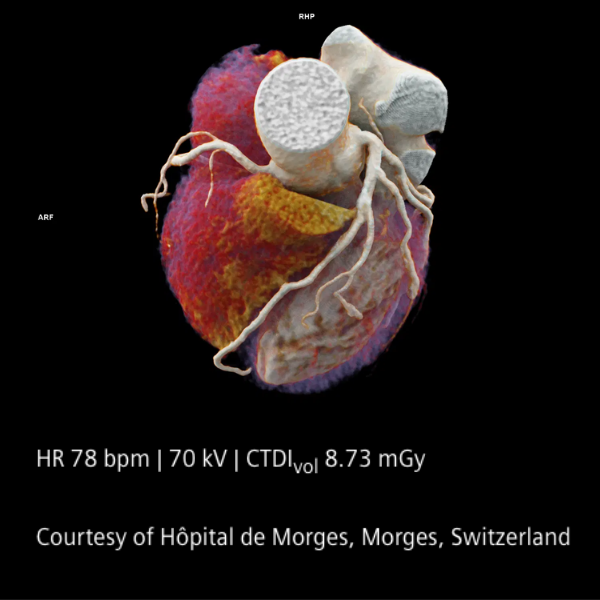

En el corazón del sistema se encuentran los detectores QuantaMax, capaces de medir cada fotón individualmente y convertirlo directamente en señal eléctrica. Esto permite eliminar el ruido electrónico, mejorar la relación contraste/ruido y obtener imágenes de alta resolución espectral sin aumentar la dosis de radiación. La combinación con la tecnología Dual Source y el potente tubo Vectron X-ray garantiza un rendimiento excepcional incluso en pacientes con alto índice de masa corporal.

El NAEOTOM Alpha ofrece velocidades de escaneo ultrarrápidas y una resolución temporal nativa de 66 ms, ampliando las posibilidades clínicas en cardiología, oncología, neurología y estudios complejos. Sus flujos de trabajo asistidos por inteligencia artificial optimizan la operación y apoyan la toma de decisiones clínicas.